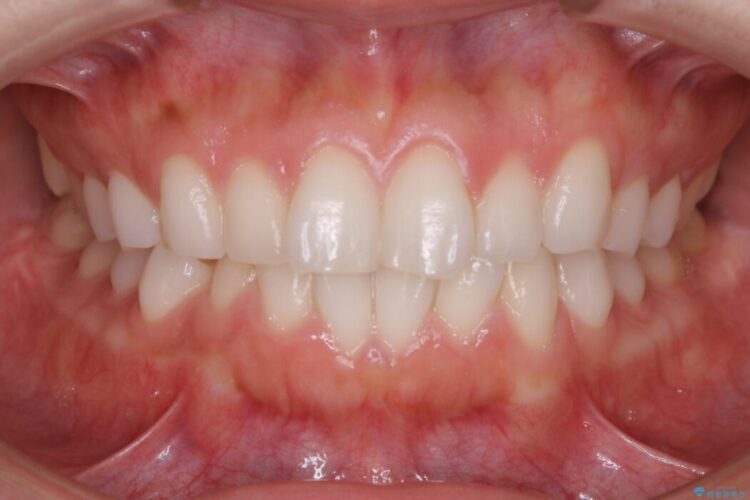

上下前歯のねじれなどで生じている歯列のガタつきをなおしたいとのことで来院されました。

半年という短期間でスピード治療が完了しました。

治療期間、治療後の出来ともに大変ご満足いただけました。